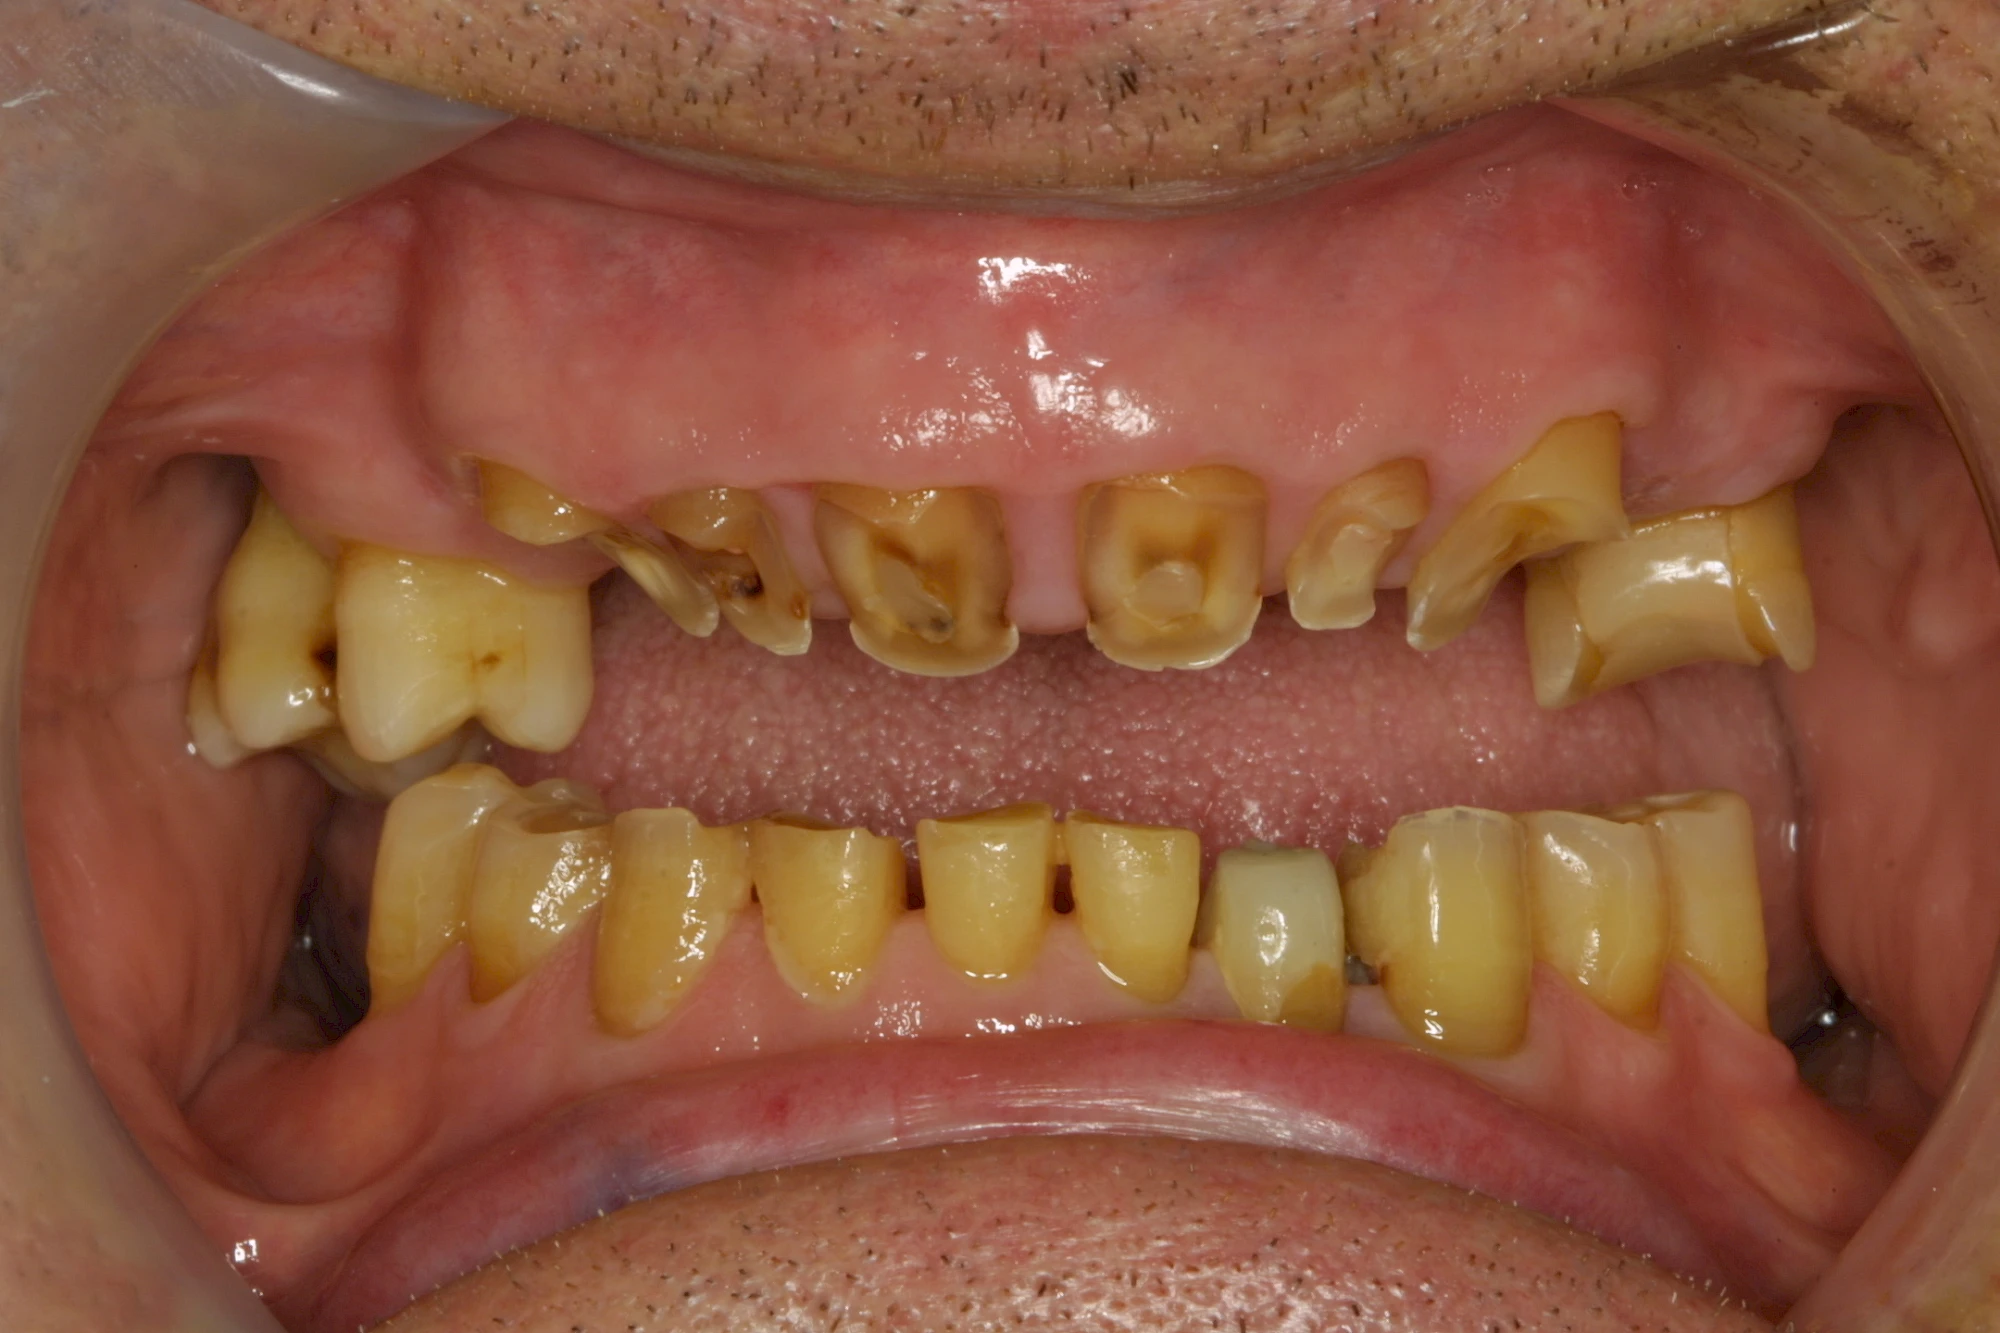

Über die Zeit können verschiedene Prozesse die Zahnhartsubstanzen aufzehren:

- Abnutzung durch Kauen (Abrasion) oder duch durch übermäßiges Knirschen bzw. Pressen (Attrition)

- Säurebedingte Auswaschung (Erosion)

- Knirschen bzw. Pressen und ungünstige Putztechnik (Druck): keilförmige Defekte

Die Zähne können dabei auf Reize (warm, kalt, süß, sauer) oder auch beim Zähneputzen empfindlich oder schmerzhaft sein. In allen diesen Fällen ist es sinnvoll, den Zahnarzt zu kontaktieren und das weitere Vorgehen abzustimmen.

Auswaschung (Erosion) dagegen ist eine Verschleißerscheinung der Zähne aufgrund von immer wiederkehrenden Säureangriffen durch die Nahrung, verstärkt zum Beispiel durch den Genuss säurehaltiger Getränke oder Speisen. Auch bei Menschen mit einer Essstörung (z. B. Bulimie) können die Zähne durch die Magensäure ausgewaschen erscheinen.